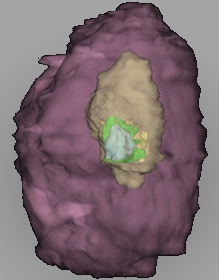

Carnegie Embryo #8004 | Location: 11-05-03

Keywords: disrupted endometrial epithelium, lumen of endometrial gland, maternal blood cells in lacunae, syncytiotrophoblast, syncytiotrophoblast engulfing endometrial gland cells

Source: The Virtual Human Embryo.